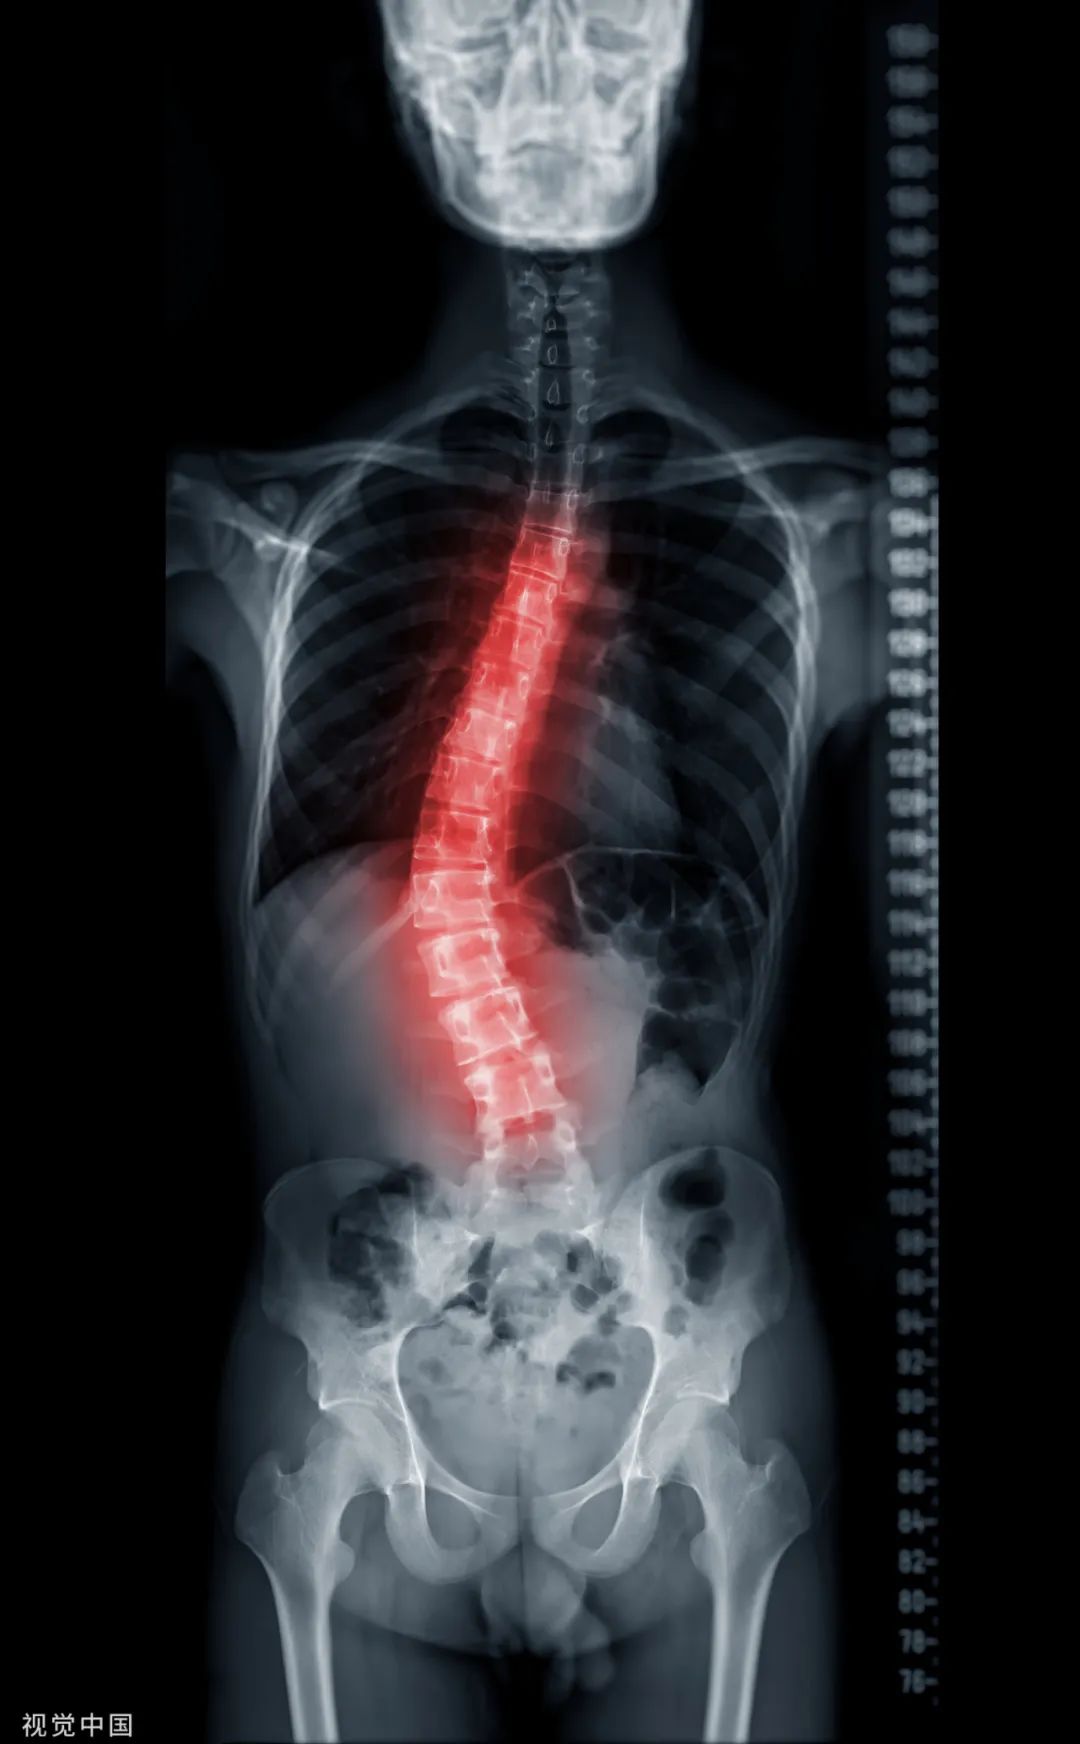

脊柱侧弯是青春期最易出现的一种骨病,会表现出明显的脊柱、体态变形。

![图片[2]-感觉自己变矮了?别大意,可能是骨骼在发出警报!-同舟](https://zb.amz114.top/wp-content/uploads/2023/12/frc-0fc81cb0da0fe1cb91aabeda9fd77da7.jpg)

此阶段要保证充足睡眠、营养和积极的体育锻炼,学习期间注意杜绝不良姿势